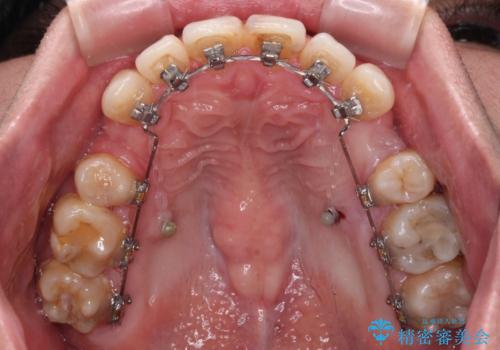

顎が左右にずれた咬み合わせ ハーフリンガルの抜歯矯正

目立たない装置を希望され、上顎が裏側装置で下顎が表側装置のハーフリンガルを希望されました。

上下の顎骨が左右に大きくずれており、奥歯が交叉咬合となっていたため、ハーフリンガルよりも表側装置をおすすめしましたが、目立たない装置を強く希望されたため、治療期間が長期化することを前提に、ハーフリンガルにて抜歯矯正を行うこととしました。

裏側装置での交叉咬合改善は非常に困難なもので、頻繁に装置の脱落がありました。